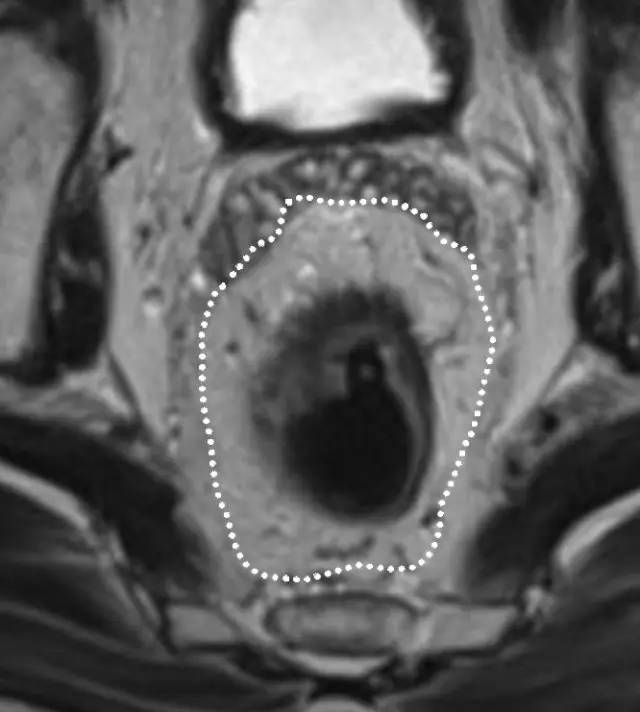

环周切缘 CRM

直肠系膜筋膜是包围直肠周围脂肪和直肠的低信号,代表 TME 切除术中的手术切除平面。在 MR 图像上,是进行 TME 手术患者的潜在 CRM。CRM 阳性是局部复发和预后差的一个重要的独立预后因素。

图 29 轴向 T2 加权图像报告 CRM 的距离。虚线描绘了直肠系膜筋膜,这是 T3a 肿瘤的 CRM,预测 CRM 阴性